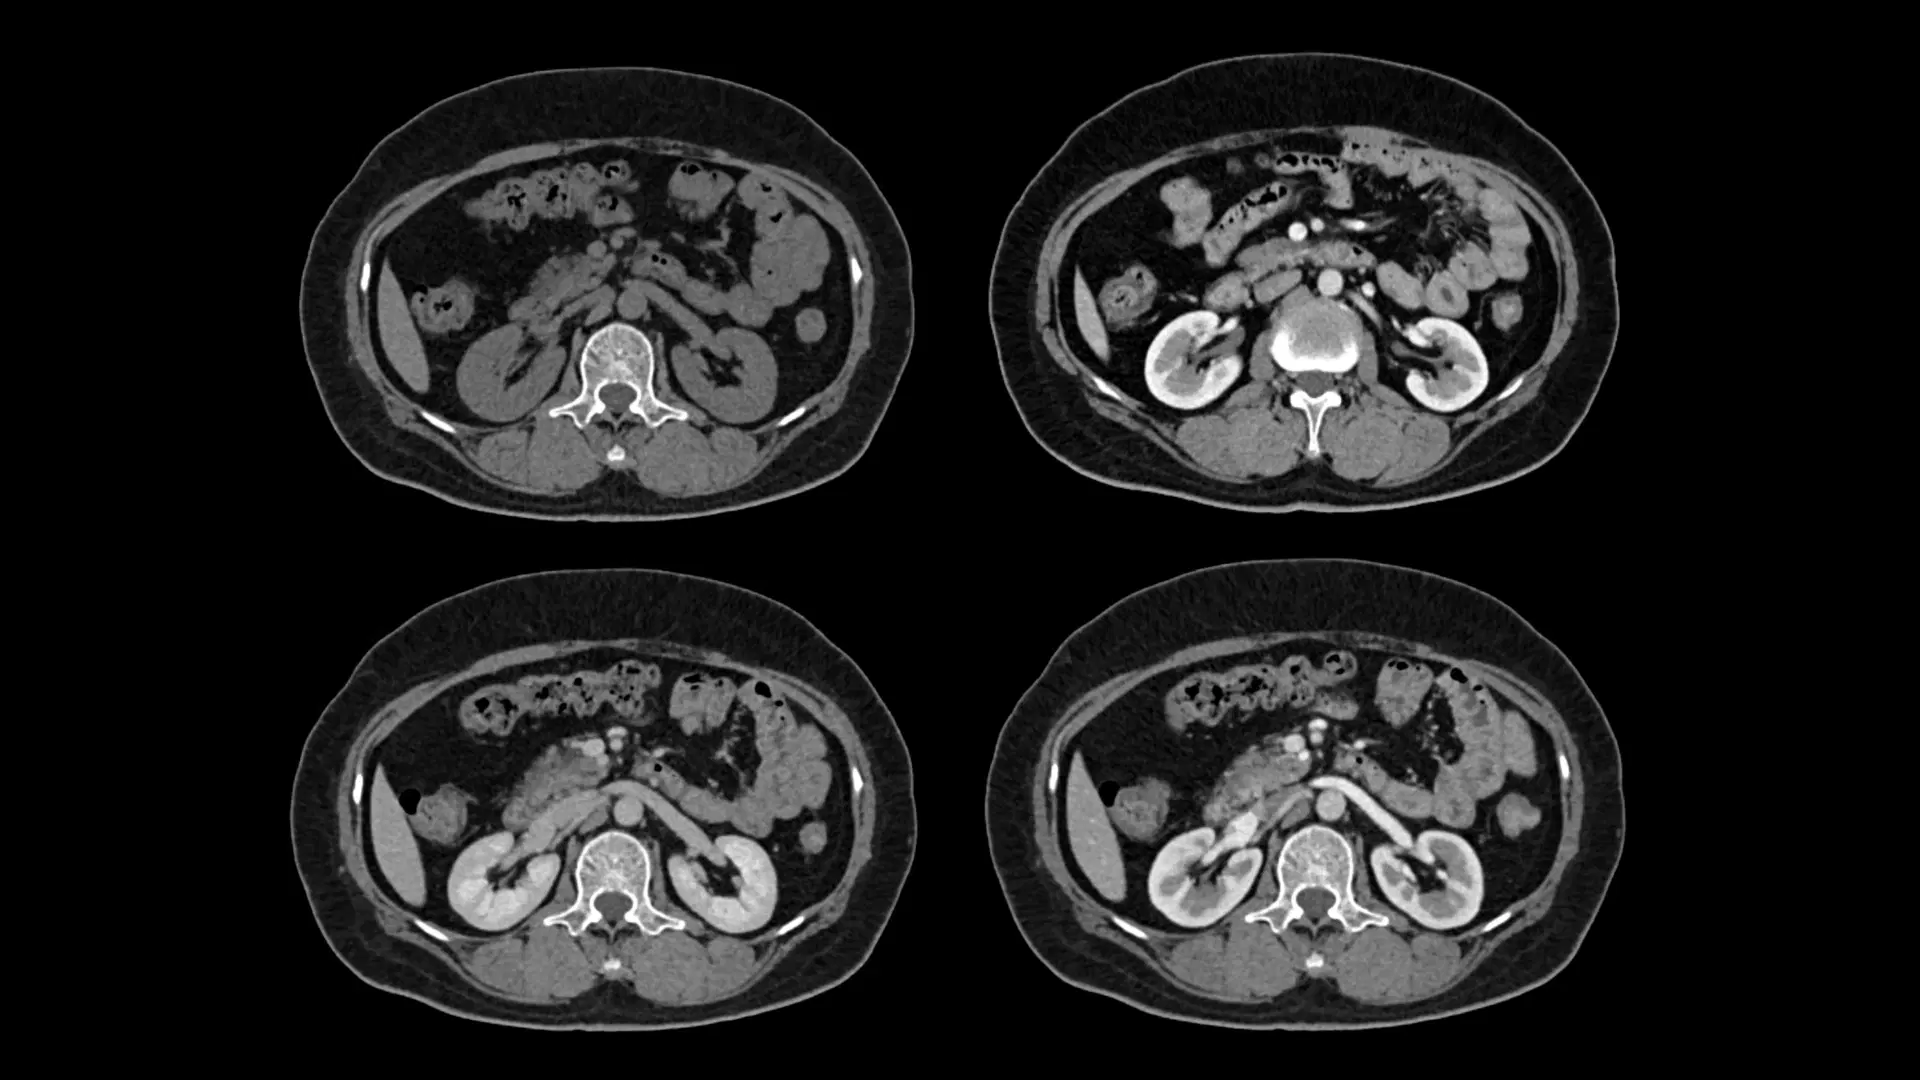

Abdomen & Pelvis CT Internal Organ Assessment Evaluates liver, kidneys, pancreas, spleen, and reproductive organs.